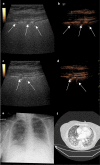

Contrast-enhanced ultrasound (CEUS) of the lung reveals multiple areas of microthrombi in a COVID-19 patient